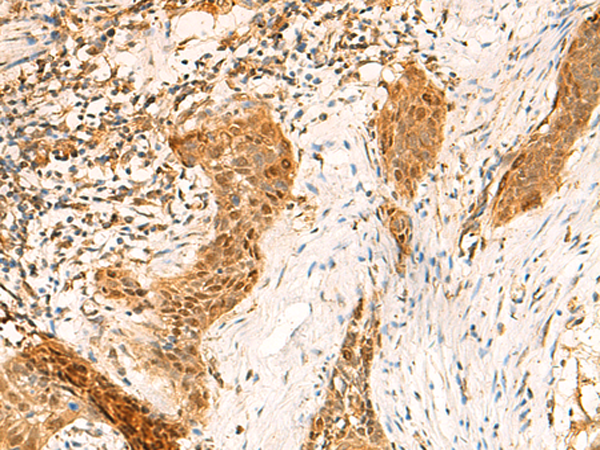

ELISA, IHC |

IHC positive control: |

Human esophagus cancer |

IHC Recommend dilution: |

50-300 |